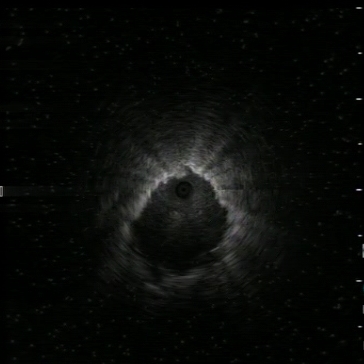

Radial US: nodule visualisation

Radial US: nodule visualisatio…